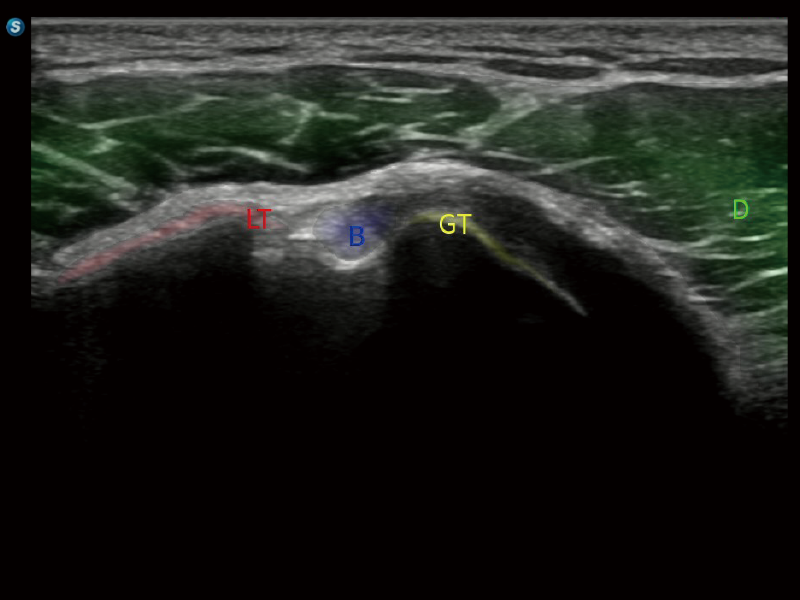

S80 提供多樣化超聲成像技術(shù),可滿足不同科室的需求,在助力掃查診斷和介入治療中發(fā)揮著重要作用。